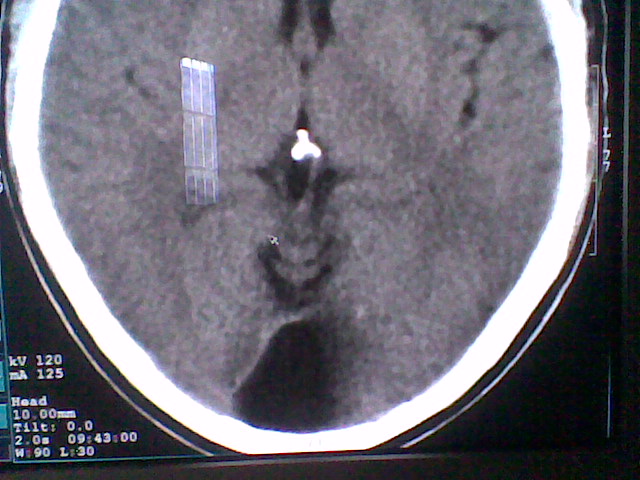

患者,男,头晕4天来诊,要求ct。

大枕大池合并蛛网膜囊肿。

支持 大枕大池合并蛛网膜囊肿。

考虑大枕大池合并蛛网膜囊肿。

有没有dandy-walker综合征的可能?